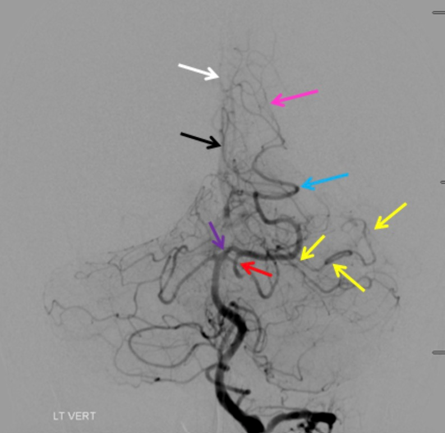

Can you name the branch marked by the black arrow? It is a paramedian branch that sits just above the tentorium. Be sure to comment your answer and check back on Thursday!

#neurotwitter #neuroanatomy #endovascular @esmintsociety @cvsection